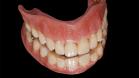

Ein Zahnimplantat ist eine künstliche Zahnwurzel aus Reintitan, die dauerhaft in den Kieferknochen eingesetzt wird. Durch den Prozess der Osseointegration verwächst das Implantat fest mit dem Knochen und bildet eine stabile Basis für Zahnersatz wie Kronen, Brücken oder Prothesen.

Ein vollständiges Implantat besteht aus: